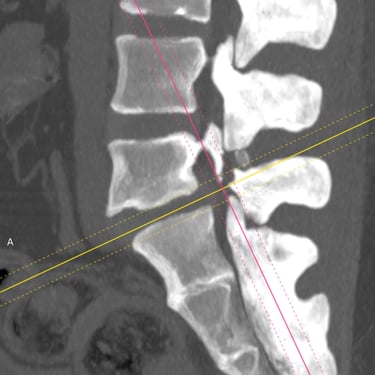

Listesis Lumbar L5–S1 por Fractura Ístmica: Estabilización con FTP y TLIF

La listesis lumbar L5–S1 por fractura ístmica se produce por un defecto en la pars interarticularis que genera inestabilidad vertebral, dolor lumbar crónico y compromiso radicular. Cuando el tratamiento conservador no es efectivo, la artrodesis lumbar con fijación transpedicular (FTP) asociada a la fusión intersomática transforaminal (TLIF) es una alternativa quirúrgica eficaz. Este procedimiento permite descomprimir las raíces nerviosas, restaurar la alineación vertebral y lograr una fijación sólida del segmento afectado. La combinación de estabilización y fusión reduce el dolor, mejora la función y favorece una recuperación segura y progresiva.